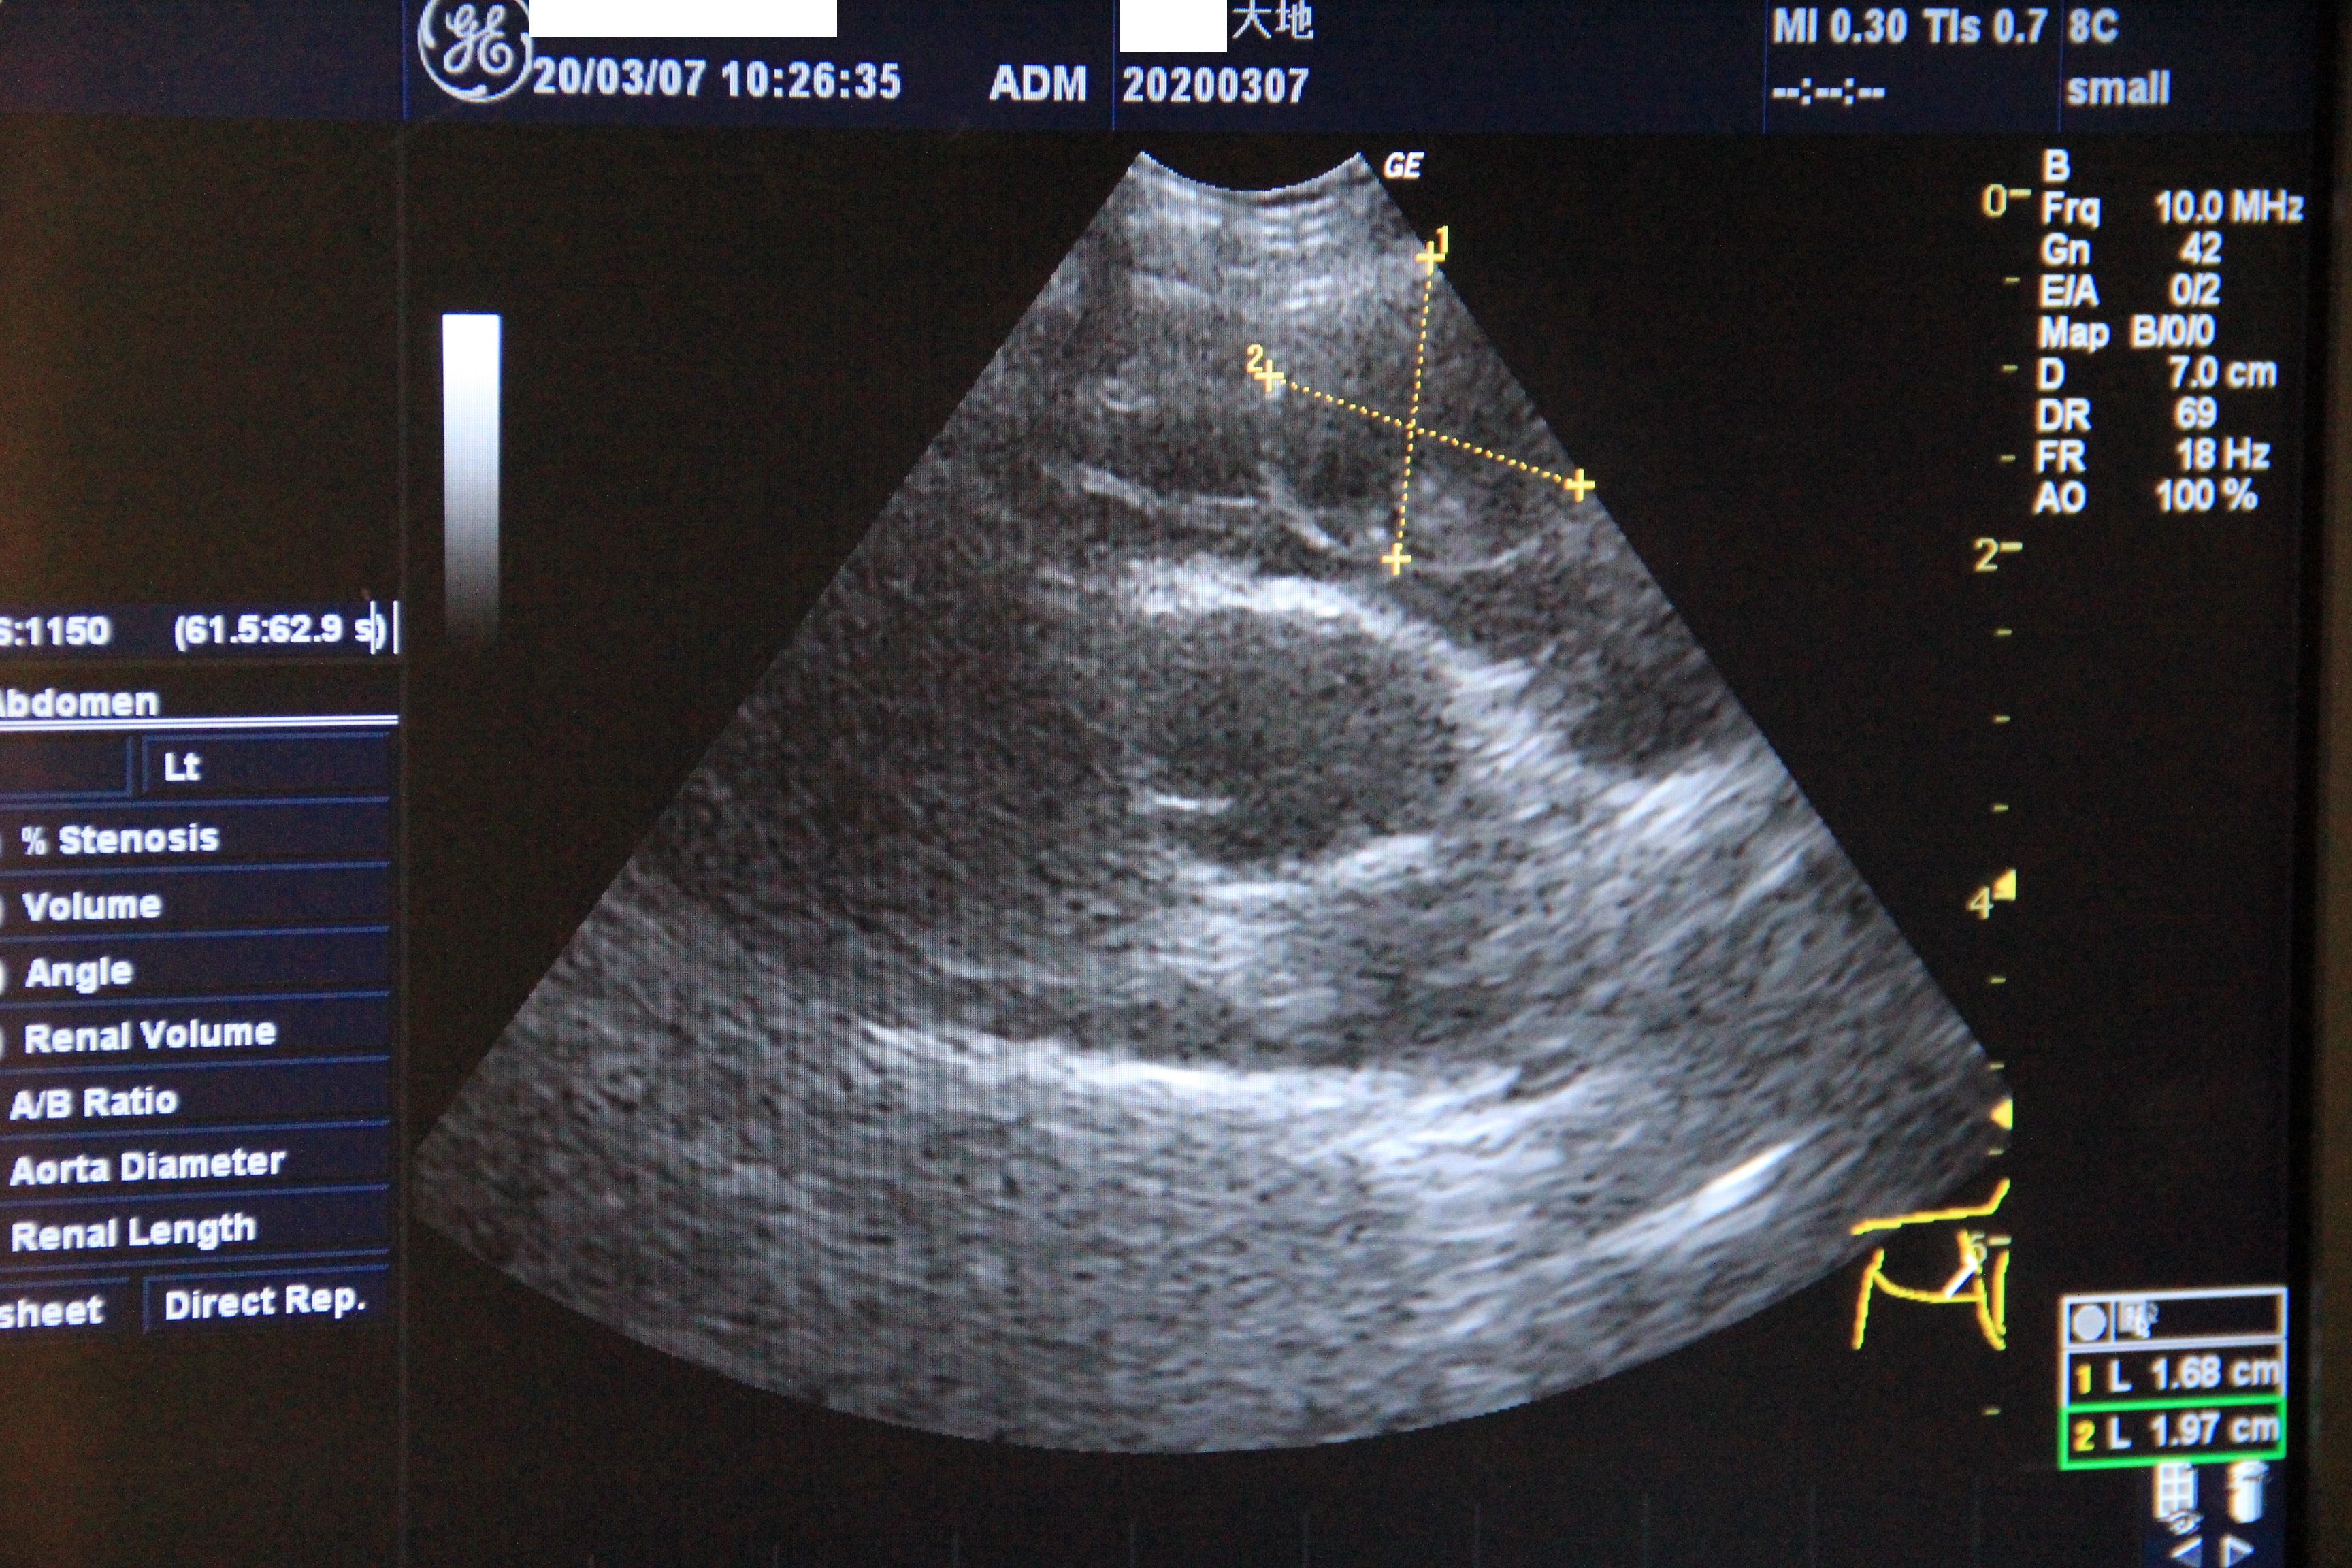

【3/7、『心臓血管肉腫による心タンポナーデ』4日後】

先生と一緒に元気いっぱい動いてる大ちゃんの心臓をエコーで確認

(血は溜まっていませんでした)

そこにある腫瘍は約1.68cm×1.97cm

こちらの病院でも腫瘍の位置から『血管肉腫』との見立てでした。